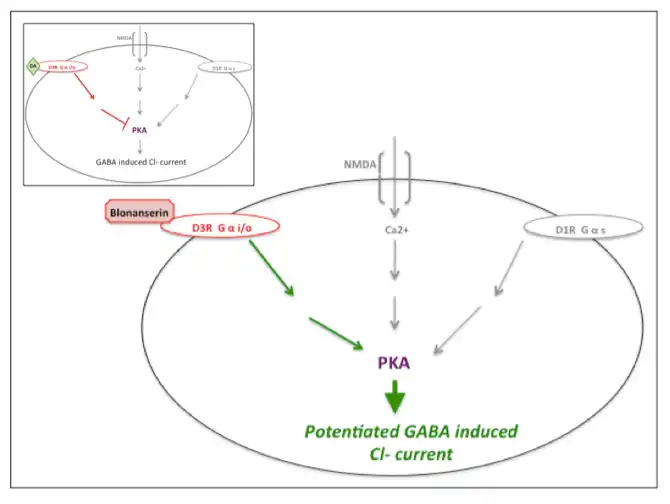

Action at the Dopamine-D3 receptor

Blonanserin has antagonistic action at dopamine-D3 receptors that potentiates phosphorylation levels of Protein kinase A (PKA) and counteracts decreased activity at the dopamine-D1 and/or NMDA receptors, thus potentiating GABA induced Cl- currents.[9][12] Olanzapine does not appear to affect PKA activity.[9][13] Many antipsychotics, such as haloperidol, chlorpromazine, risperidone and olanzapine primarily antagonize serotonin 5-HT2A and dopamine-D2 receptors and lack known action at dopamine-D2/3 receptors.[9][10]

| Blonanserin action at dopamine-D3 receptor. Cartoon of blonanserin's antagonistic impact at the dopamine-D3 receptor, reversing inhibition of PKA activity (also regulated by dopamine-D1 and NMDA activity) thus potentiating GABA induced Cl- current. Inset illustrates uninterrupted dopamine (DA) activity at the dopamine-D3 receptor. Inspired by Hida et al. (2014) and Yokota et al. (2002).[9][12] |